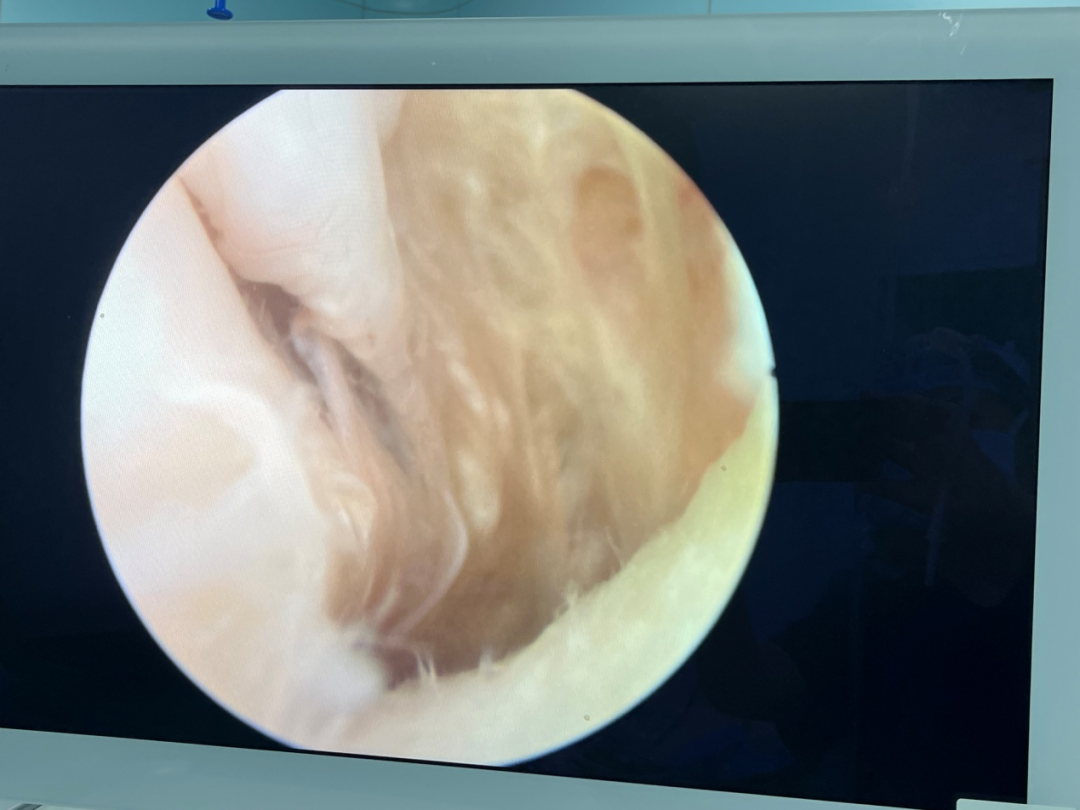

术中关节镜下切除腘窝囊肿

修补成形外侧半月板

术中通过3个仅0.5cm长的微创切口,在膝关节镜下成功切除了腘窝囊肿,并修补成形外侧半月板,快速恢复膝关节半月板稳定性,安全、有效地解决了张女士的困扰。